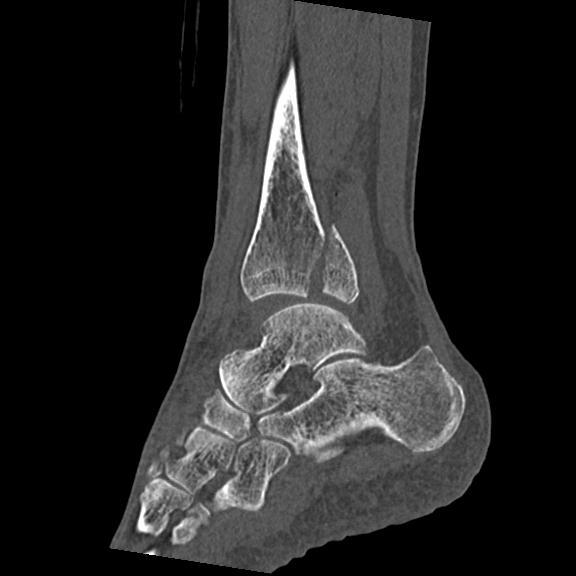

102755 1/4 2R 1/15 2R 右足関節 68歳女性 右三果脱臼骨折